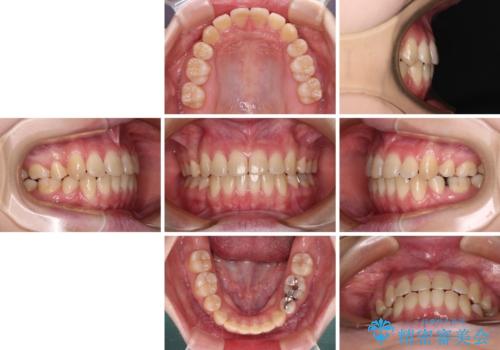

上下の出っ歯を治したい ワイヤー装置による抜歯矯正

- 上下前歯が前方に飛び出しているとのことで来院された患者様です。

上下左右第一小臼歯4本を抜歯して、積極的に口元を引っ込めるよう、ワイヤー装置にて矯正治療を行うこととしました。

口元の突出感は著しく改善され、横顔の印象が大きく変化しました。